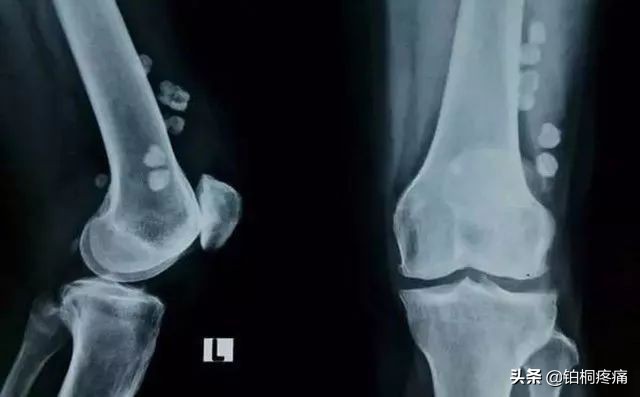

01、骨关节炎

中老年人常出现膝盖红肿痛、上下楼梯痛、坐起立行时膝部酸痛等不适,在休息后缓解。如果拍片子发现关节磨损、骨质增生、关节间隙变狭窄,甚至出现关节畸形,说明膝关节退化到了骨关节炎的阶段,已经不可逆转,需要引起重视。轻者可采取康复、止痛治疗,稍严重者可进行疼痛科专有微创介入治疗。